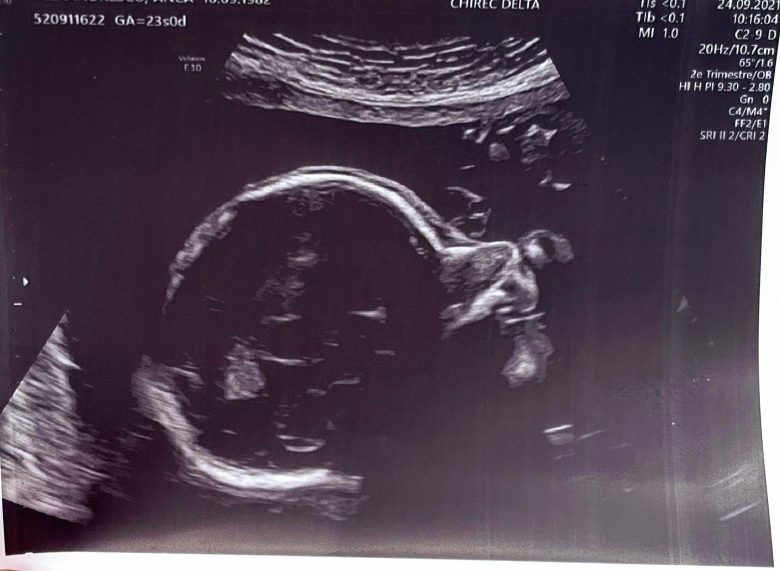

The second trimester morphological ultrasound was incredibly technical and detailed. Happily, all was within parameters. I don’t remember having done a special ultrasound during my first pregnancy. Back then, it felt like all our monthly ultrasounds were incredibly detailed (much more so than the routine ones this time), so maybe there was no need and our doctor was specialised in this.

The gynae came in, with the blood results and part of the urine test. Nothing extraordinary. A little anaemia, which wasn’t unusual. All pointed to a gastro virus possibly combined with a urinary infection. Nothing worrying so far. She did an ultrasound, including the first transvaginal ultrasound since the very beginning of the pregnancy. All looked fine with the baby, but my cervix was shortened (27 mm, below the 30 mm normal lower range) and showed signs of opening.